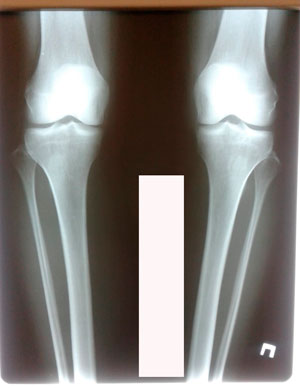

Исходник - 40 лет

Диагноз: варусная деформация голеней + Ротация с обеих сторон.